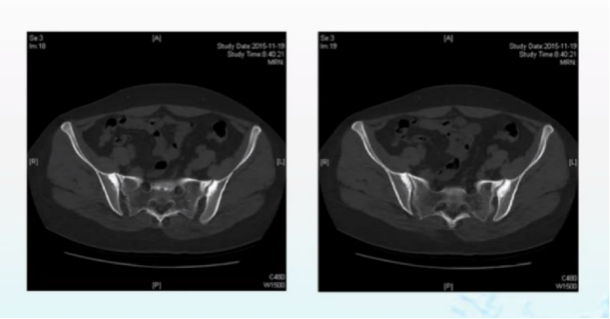

骶髂关节CT示:骶髂关节近关节区域硬化,关节边缘清晰,无关节间隙变窄。

患者的炎性指标升高,并且有持续的腰骶部疼痛,确实很有迷惑性,让人禁不住和AS联系起来。但CT结果一出来,瞬间就可以把AS排除了。这是为啥?这就得来了解AS患者骶髂关节的CT表现了!

这样一看,该名患者的CT关节边缘清晰,无关节间隙变窄,显然并不符合AS特征性的骶髂关节改变。最终,患者被诊断为致密性骨炎,在接受塞来昔布、局部理疗等治疗后得到明显缓解。